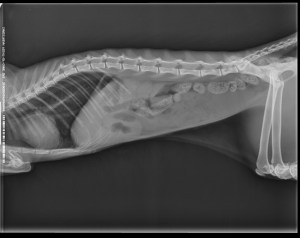

Patient: 3 yo male spayed Persian cat.

History: Vomiting, anorexia and weight loss since one week. Blood tests were with no clinical significance.

Findings: Α distention of the small intestine was noted. A corrugated small intestinal loop was found (pic1), which led to an acoustic shadow (pic2-3). This was because of an intraluminal foreign body, which was causing a partial obstruction of the small intestine.

Treatment: Surgical removal of the foreign body(pic4).

Ακτινογραφία πριν τον υπέρηχο(Xray made prior to the U/S)